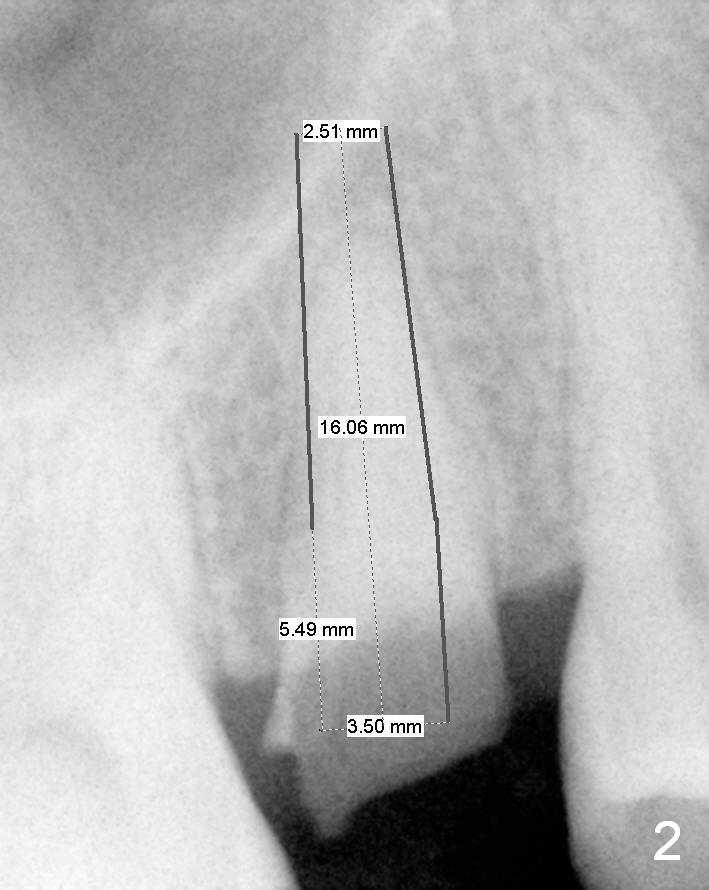

A 52-year-old woman (LP) has postponed extraction and implant for the tooth #4 for 10 years (Fig.1). The socket is oval in cross section, great site for D Implant. D2 (3.5x4.5 mm) short (16 mm, Fig.2) and long (20 mm, Fig.3) implants appear to be fit for the site (no antibiotic). However, placement of the latter involves bone expansion/tapping, which is incompatible with the fearful lady. Let us be gentle (Fig.4).